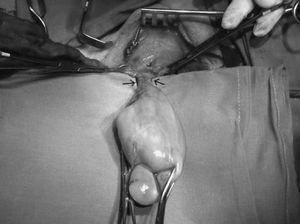

Fig. 2. Cirugía: lipoma exteriorizado por cervicotomía con base de implantación.

Paciente de 73 años, con antecedentes de exéresis de pólipos faríngeos hace 8 y 18 años y exéresis de lipoma de seno piriforme hace 6 meses, que es remitido por el otorrinolaringólogo por persistencia de clínica de disfagia alta tras la cirugía, sin otros síntomas. Se le practica una endoscopia digestiva, que informa de tumor submucoso de 8 cm en el tercio superior de esófago, que afecta desde boca de Killian hasta tercio medio esofágico. Con la sonda de ecoendoscopia se visualiza una masa ecogénica de 1,5 cm de diámetro que procede de submucosa e indica lipoma esofágico. En el tránsito baritado se aprecia un defecto de repleción de unos 10 cm de longitud que ocupa la totalidad de la luz esofágica (fig. 1). En la resonancia magnética se visualiza una tumoración del mediastino posterior hiperintensa en las imágenes potenciadas en T1 y T2, cuyo polo superior depende de esófago cervical. La tomografía computarizada cervicotorácica informa de una tumoración cervical intraesofágica de 10 × 3,5 × 4 cm, de características radiológicas compatibles con tejido graso. Ante estos hallazgos se decidió intervención quirúrgica. Mediante un abordaje por cervicotomía lateral izquierda, se procedió a la disección del esófago cervical y esofagotomía longitudinal; se visualizó una masa elástica que ocupaba la totalidad de la luz esofágica y se procedió a su extracción. La tumoración medía unos 10 cm, con una base de implantación fina en la pared posterior del esófago cervical (fig. 2). Se procedió a resección y posterior esofagorrafia. El postoperatorio fue satisfactorio, y se dio el alta al sexto día.